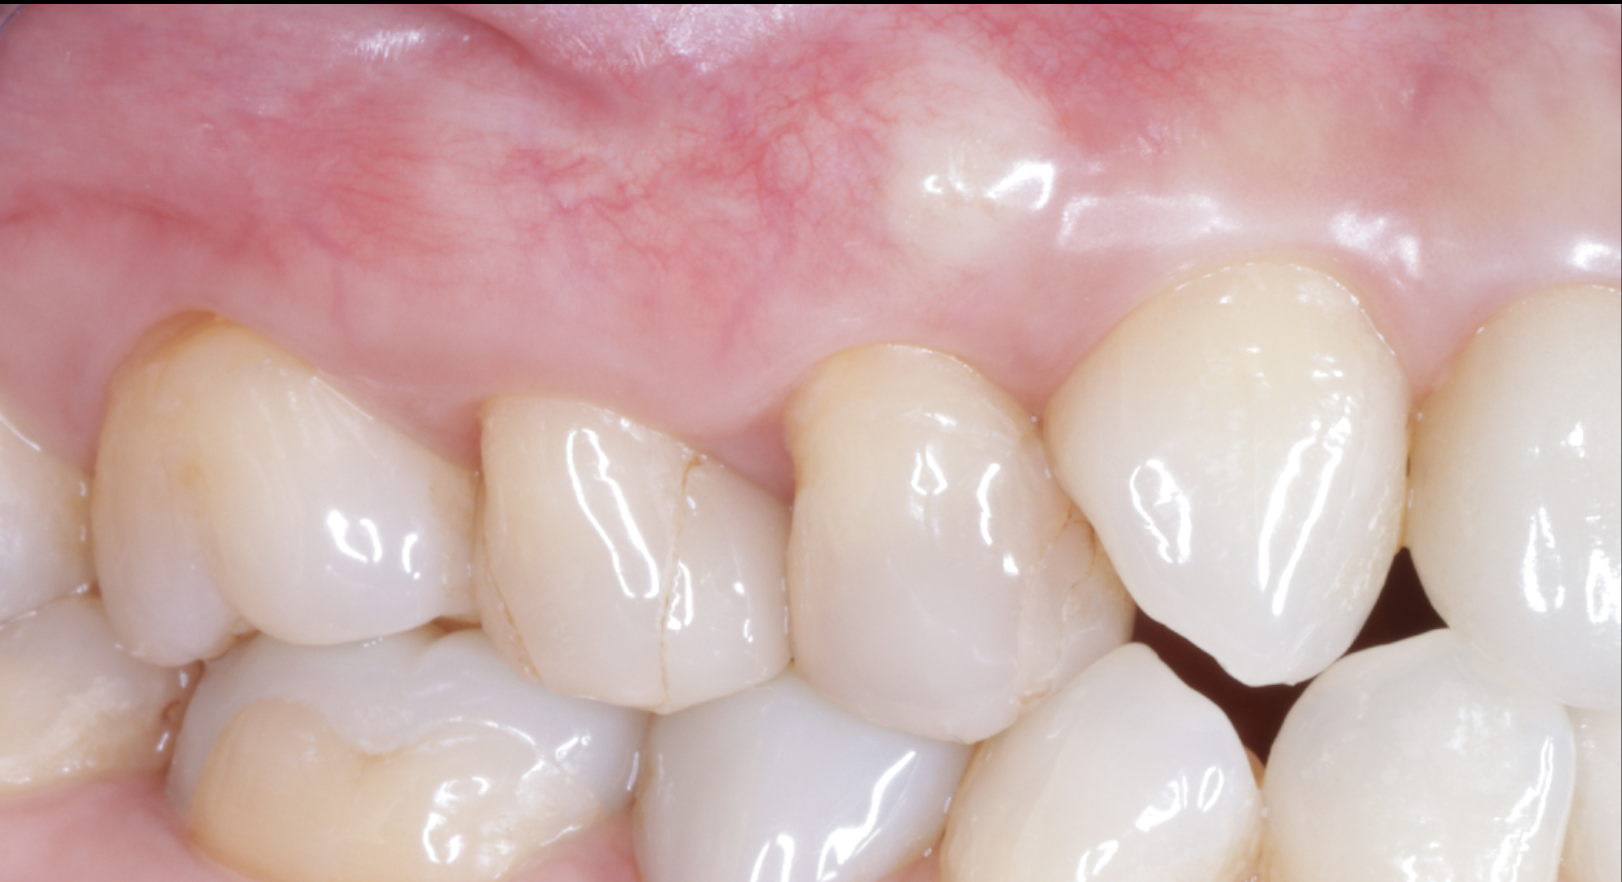

前歯の破折と虫歯をダイレクトボンディングで修復した症例|池袋で精密な審美修復

- 主訴

- 前歯の欠け、虫歯を治したい

- 1回(90分)

- 22万(4前歯)

- ダイレクトボンディング

- レジンのチップ

劣化